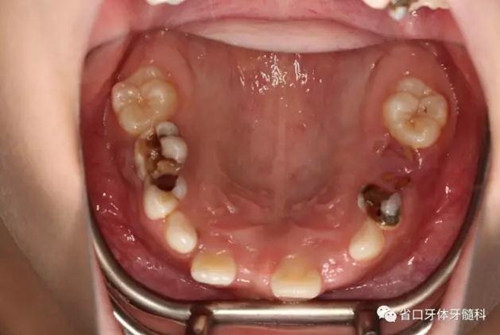

檢查:替牙列,12、21已萌出,11、22未萌,12、21間隙約5mm,右上前牙區(qū)前庭溝處見黏膜隆起,11牙冠未破齦。

口內(nèi)情況:正面觀

口內(nèi)情況:牙合 面觀